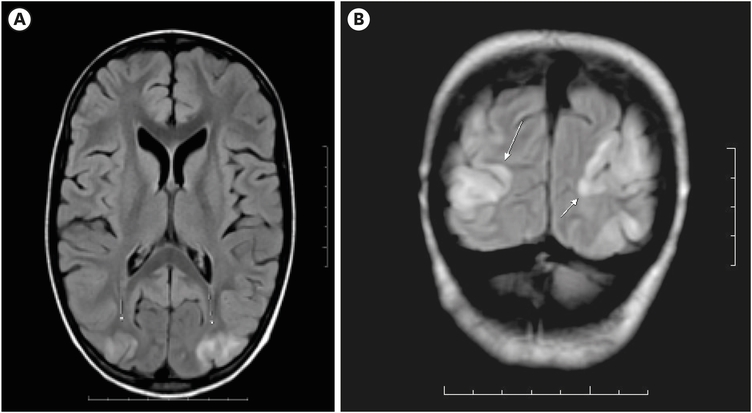

On the postoperative day (POD) 2, the patient had multiple spikes of fever with leukopenia. Antibiotics were escalated. On POD 6, the patient had a headache and blurring of vision with elevated blood pressure (134/110 mmHg). Tab Amlodipine, 2.5 mg stat, was administered. Due to persistent high blood pressure recordings, inj. Labetalol infusion was started. On POD 7, magnetic resonance imaging (MRI) revealed T2/ FLAIR hyperintensity in bilateral parieto-occipital lobes with restricted diffusion and minimal heterogeneous leptomeningeal enhancement (Fig. 2). The clinical and radiological features were representative of PRES. The patient was treated with intravenous fluids, antibiotics, anti-hypertensive drugs, and supportive care in the pediatric Intensive care unit. There was a gradual clinical improvement with decreased headache and improved vision on POD 9. Labetalol infusion was stopped on POD 10, and adequate blood pressure control was obtained with Tab. Amlodipine 2.5 mg per day. The patient’s vision had improved, and she was discharged on POD 12.

Fig. 2

Magnetic resonance imaging brain showing features characteristic of posterior reversible encephalopathy syndrome. (A) Axial and (B) coronal views. Bilateral symmetrical parieto-occipital white matter hyperintensities (indicated by arrow mark in B).

MRI reveals distinct features, primarily characterized by bilaterally symmetrical parieto-occipital white matter hyperintensities. Some cases may show atypical features such as hemorrhage and restricted diffusion [1]. While the parieto-occipital lobes are most frequently affected, other areas like the frontal lobes, cerebellum, and temporal lobes can also be involved. In some instances, atypical regions such as the basal ganglia, brainstem, and thalamus may be affected [1].